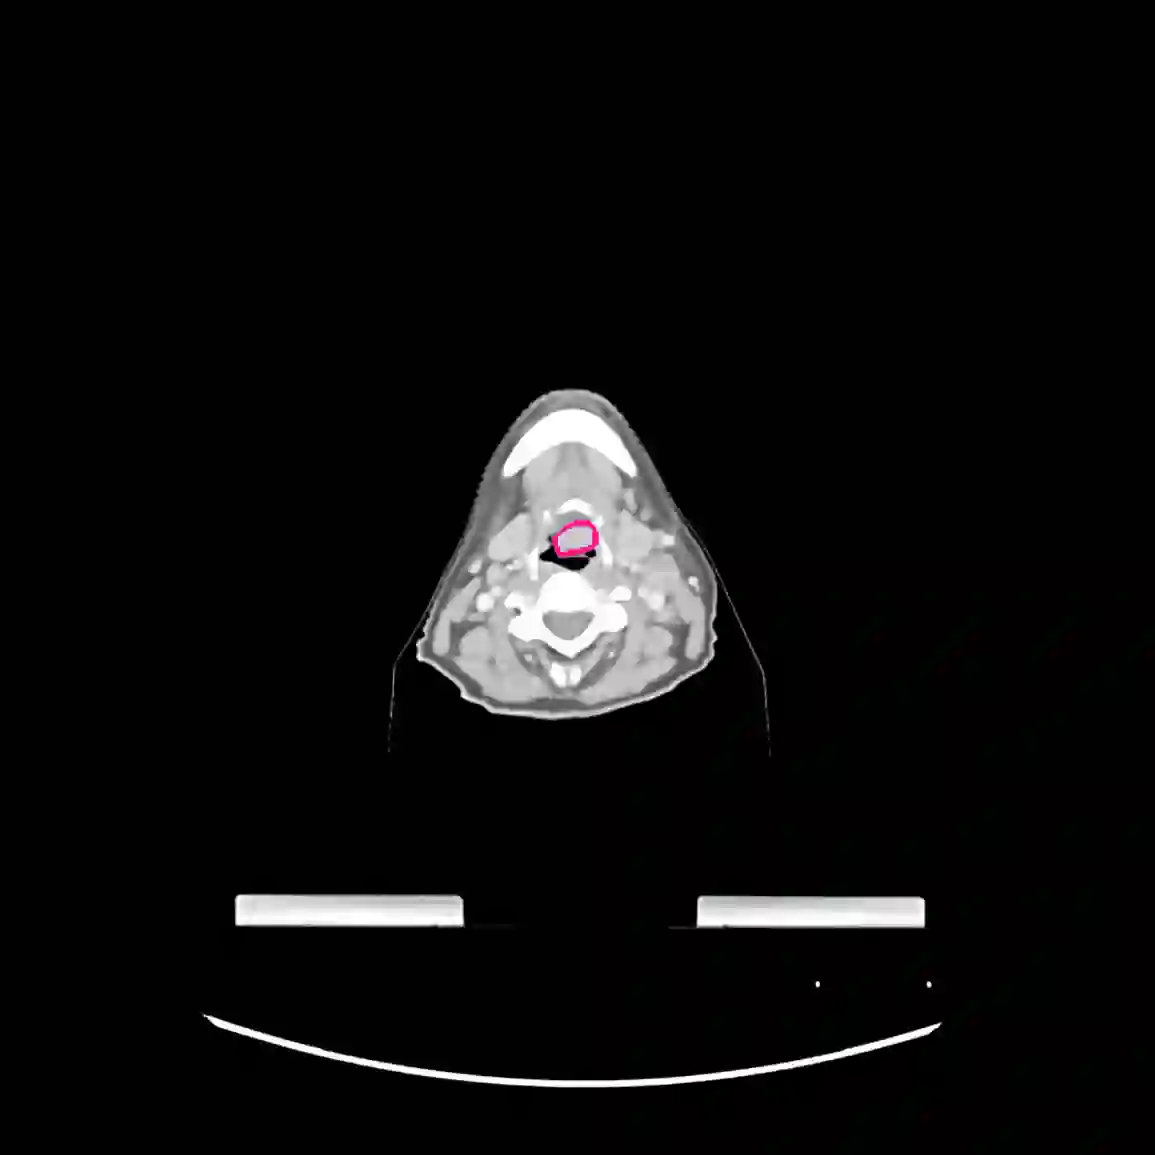

Radiomics uses quantitative medical imaging features to predict clinical outcomes. Currently, in a new clinical application, finding the optimal radiomics method out of the wide range of available options has to be done manually through a heuristic trial-and-error process. In this study we propose a framework for automatically optimizing the construction of radiomics workflows per application. To this end, we formulate radiomics as a modular workflow and include a large collection of common algorithms for each component. To optimize the workflow per application, we employ automated machine learning using a random search and ensembling. We evaluate our method in twelve different clinical applications, resulting in the following area under the curves: 1) liposarcoma (0.83); 2) desmoid-type fibromatosis (0.82); 3) primary liver tumors (0.80); 4) gastrointestinal stromal tumors (0.77); 5) colorectal liver metastases (0.61); 6) melanoma metastases (0.45); 7) hepatocellular carcinoma (0.75); 8) mesenteric fibrosis (0.80); 9) prostate cancer (0.72); 10) glioma (0.71); 11) Alzheimer's disease (0.87); and 12) head and neck cancer (0.84). We show that our framework has a competitive performance compared human experts, outperforms a radiomics baseline, and performs similar or superior to Bayesian optimization and more advanced ensemble approaches. Concluding, our method fully automatically optimizes the construction of radiomics workflows, thereby streamlining the search for radiomics biomarkers in new applications. To facilitate reproducibility and future research, we publicly release six datasets, the software implementation of our framework, and the code to reproduce this study.